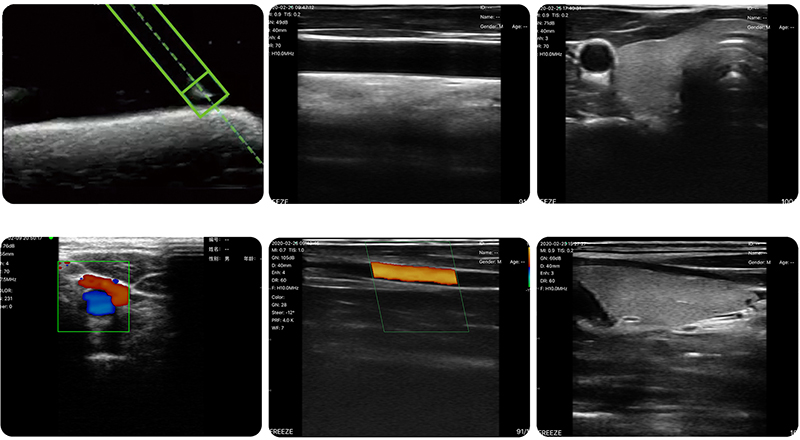

The built-in magnetic sensor in the palm ultrasound captures the environmental magnetic field vector and the magnetized needle's induced magnetic field vector. This information is then transmitted to the processing unit for calculating the displacement and angle of the needle, followed by generating a pattern displaying this displacement and angle information overlaid onto the ultrasound image for simultaneous visualization.

Ultrasonic imaging displays the puncture needle superimposed by magnetic field displacement, and the Angle positioning displays the puncture needle to realize more reliable visualization of the puncture needle with multi-directional and cross-verification, which makes the puncture more accurate, improves the success rate of puncture intervention, reduces the difficulty of puncture intervention, and makes the operation easier without relying on the puncture frame.